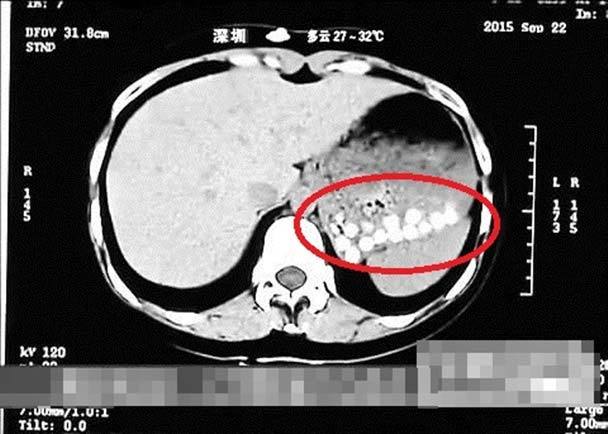

Trong khi thực hiện một chương trình về phong cách sống có tên gọi "Life Help", một phóng viên ở thành phố Thanh Đảo, thuộc tỉnh Sơn Đông đã uống trà sữa trân châu bán ở một cửa hàng địa phương. Người này sau đó bị đau bụng và phải tới một bệnh viện gần đấy để chụp cắt lớp kiểm tra.

Kết quả chụp kiểm tra hé lộ, trong bụng phóng viên chứa đầy các hạt trân châu chưa được tiêu hóa.

Kết quả chụp y tế hé lộ, trong bụng phóng viên chứa đầy các hạt trân châu chưa tiêu hóa được. Ảnh: Truyền hình Sơn Đông. |